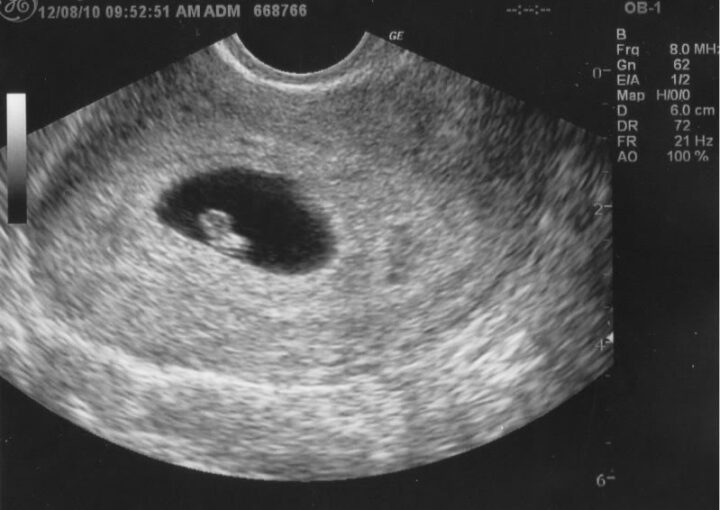

Bebeğinizin Kalbi Atmaya Başlıyor

Gebeliğin 6. haftası, embriyonun hızla gelişmeye devam ettiği ve bebeğinizin ilk kalp atışlarının duyulabileceği bir dönemi simgeler. Artık ultrasonla bebekteki kalp atışları izlenebilir, bu da anne adayları için büyük bir heyecan kaynağıdır.

6. hafta itibarıyla bebeğinizin kalbi atmaya başlar. Embriyo, bu hafta boyunca hızla gelişir ve yaklaşık 4-6 mm boyutlarına ulaşır. Embriyo, minik bir insan figürüne daha da yakınlaşmaya başlar; baş, vücut ve kolların oluşumları gözle görülür hale gelir. Kalp atışı ise ultrasonla izlenebilecek kadar güçlüdür.

Evet, bu hafta ultrasonla kalp atışları izlenebilir. Genellikle 6. haftada kalp atışı duyulmaya başlar.